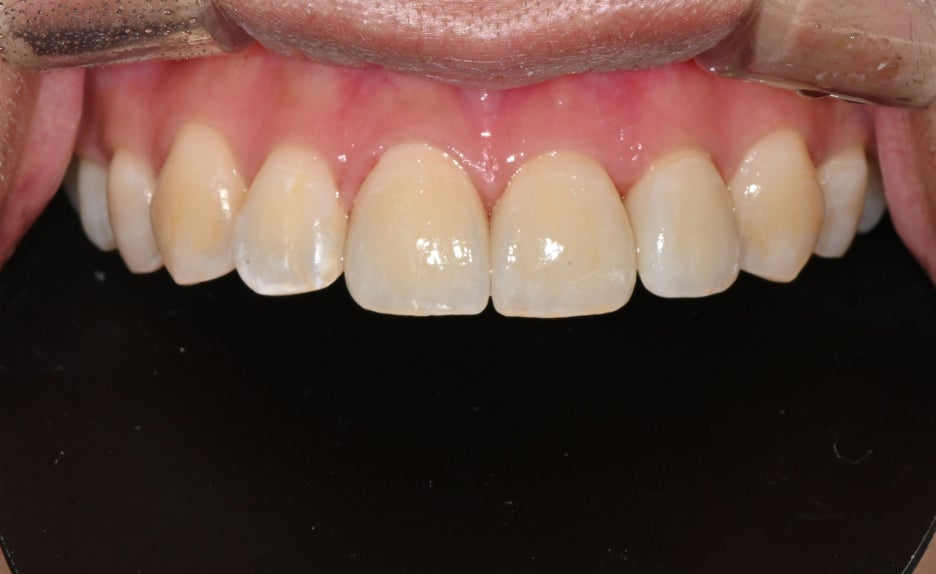

Before and after treatment photos

Photos before and after treatment

After treatment, the patient said,

“Now my front teeth are aligned again, so I feel more confident when smiling,”

and expressed satisfaction.

She also felt more reassured because people around her said it looked natural.